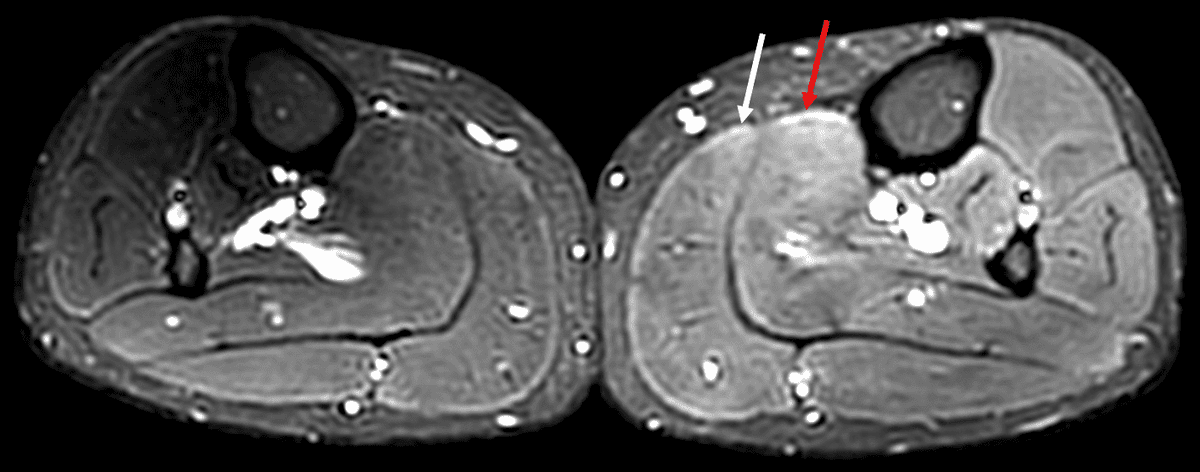

Douleurs musculaires d'apparition retardée - DOMS (Delayed Onset Muscle Soreness)